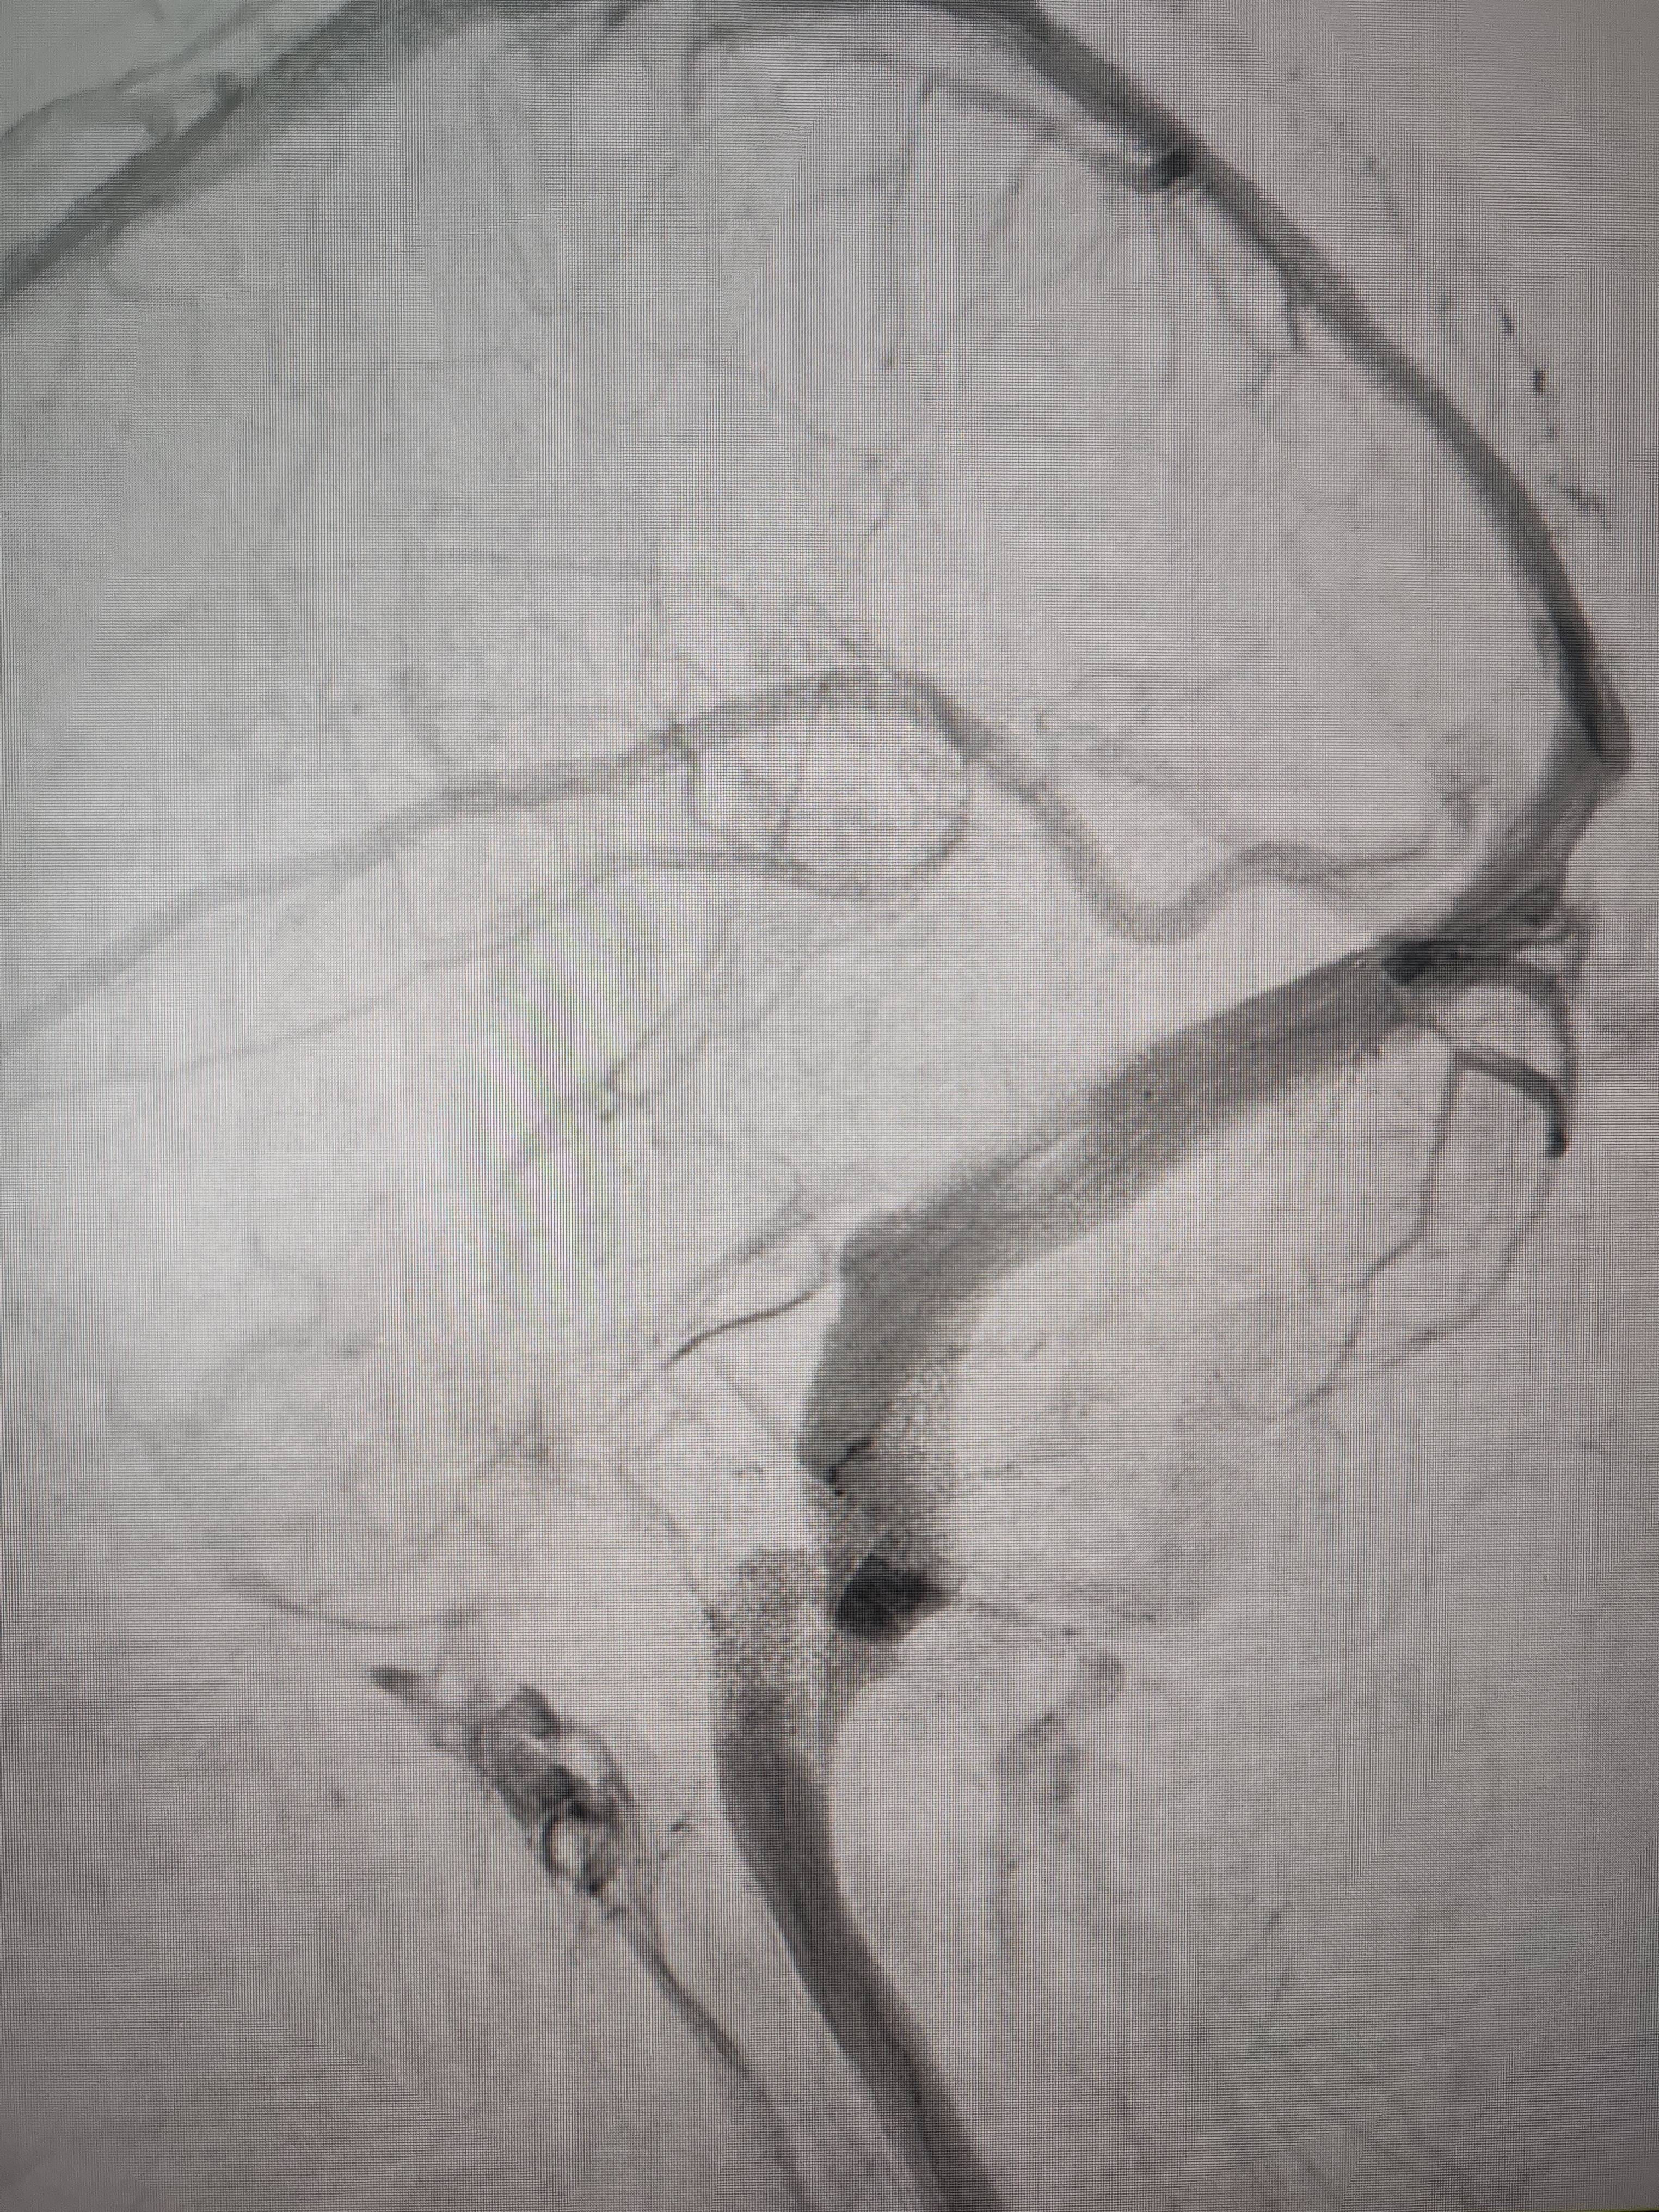

经过静脉窦支架置入手术治疗后,患者的静脉窦“堵点”被打通证券市场基础知识。 南方+ 欧阳少伟 拍摄

“从手术室出来,麻药清醒以后,我感觉整个世界都清静了,没想到效果这么立竿见影证券市场基础知识。”减轻病痛的赵女士,术后很是开心,次日就可下床自如活动,目前已康复出院。